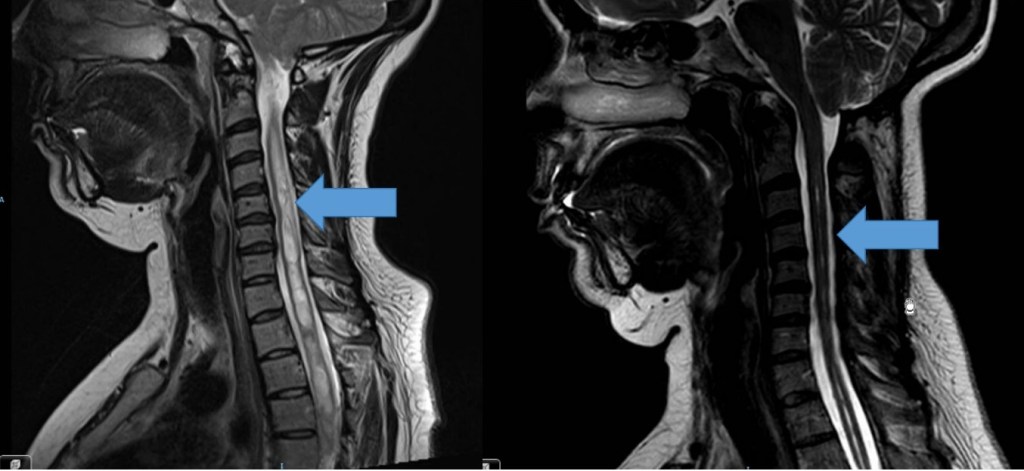

-La malformación de Chiari II (o Arnold Chiari) es prácticamente exclusiva del mielomeningocele (espina bífida). En él además de las amígdalas cerebelosas existe una herniación del resto de estructuras del tronco del encéfalo. Muy frecuentemente va a estar asociada a hidrocefalia precisando la mayoría de pacientes de derivación ventriculoperitoneal (DVP) para el tratamiento de la misma.

Su sintomatología característica es debida a la compresión del tronco del encéfalo, de manera que puede presentarse con apneas, estridor laríngeo, disfagia, episodios de broncoaspiración, debilidad en extremidades y alteraciones en la motilidad ocular.

En caso de progresión de los síntomas debe descartarse en primer lugar la presencia de hidrocefalia descompensada, generalmente debida a una malfunción del sistema de derivación de líquido cefalorraquídeo. En caso de confirmarse esto debe ser revisado quirúrgicamente el sistema de derivación. Si pese a ello o bien tras descartar la disfunción del sistema persiste la sintomatología debe entonces llevarse a cabo la descompresión quirúrgica de las estructuras de la fosa posterior.